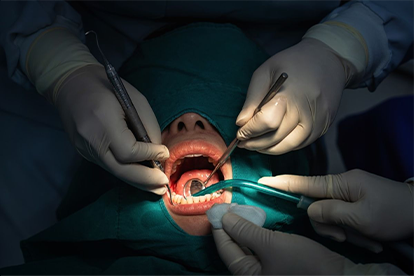

placed once healing allows, using Yomi® robotic guidance for precision in compromised bone.

implants, grafts, or maxillofacial prosthetics to restore chewing, speech, and facial contours.